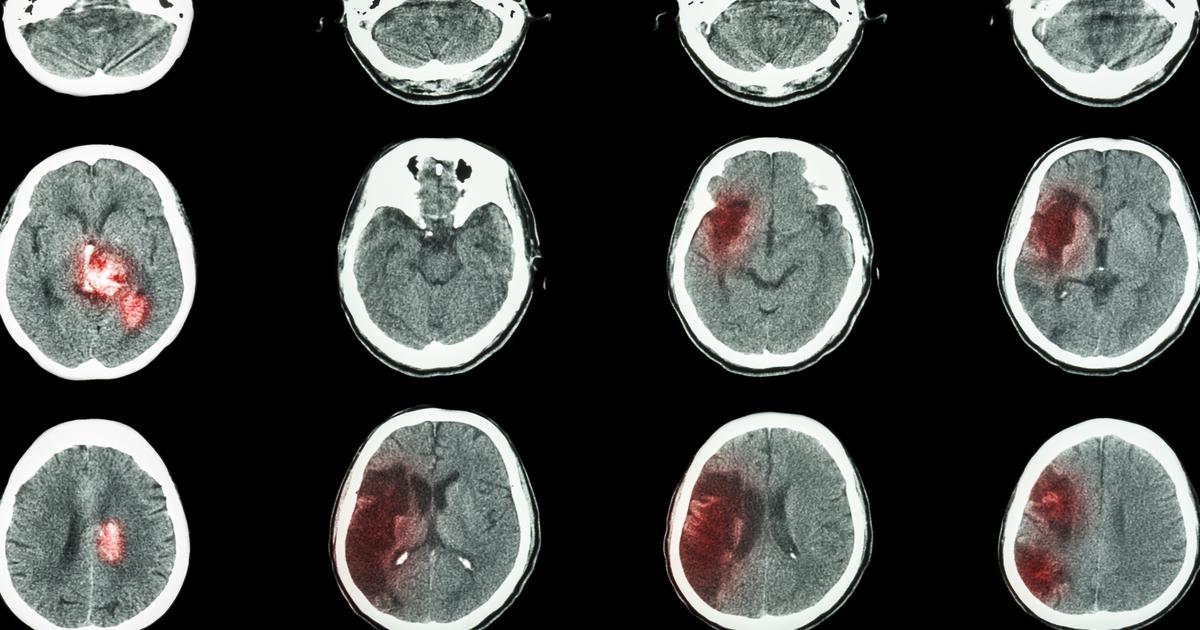

How To Treat A Subarachnoid HemorrhageA subarachnoid hemorrhage occurs when there is bleeding between the brain and the subarachnoid space surrounding it. Most cases present with a sudden and severe…November 6, 2019